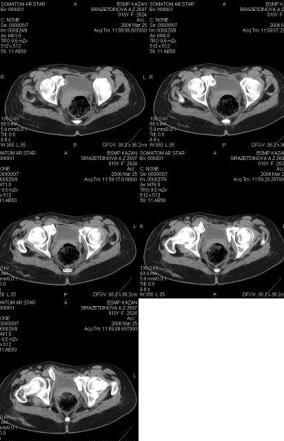

Уважаемые коллеги! Девушка 18л сросшиеся переломы лонных, седалищных костей с обеих сторон, перелом крестца справа,перелом костей голени справа (зио), 3 мес после травмы, АВФ снят с таза.

Патологической подвижности нет. Стоит самостоятельно, ходит с костылями, поскольку 3 месяца практически не ходила. Беспокоит выступание лонной кости в области лобка, хотя объективно грубого косметического дефекта нет. На кт разворот лонной кости в сагиттальную плоскость. Вопрос: стоит ли добиватьсяполной репозиции или же достаточно произвести остеотомию верхушки выступающего отломка?

Предоставляю срезы. Если пациентку функционально ничего не беспокоит, стоит ли навязывать ей лечение.